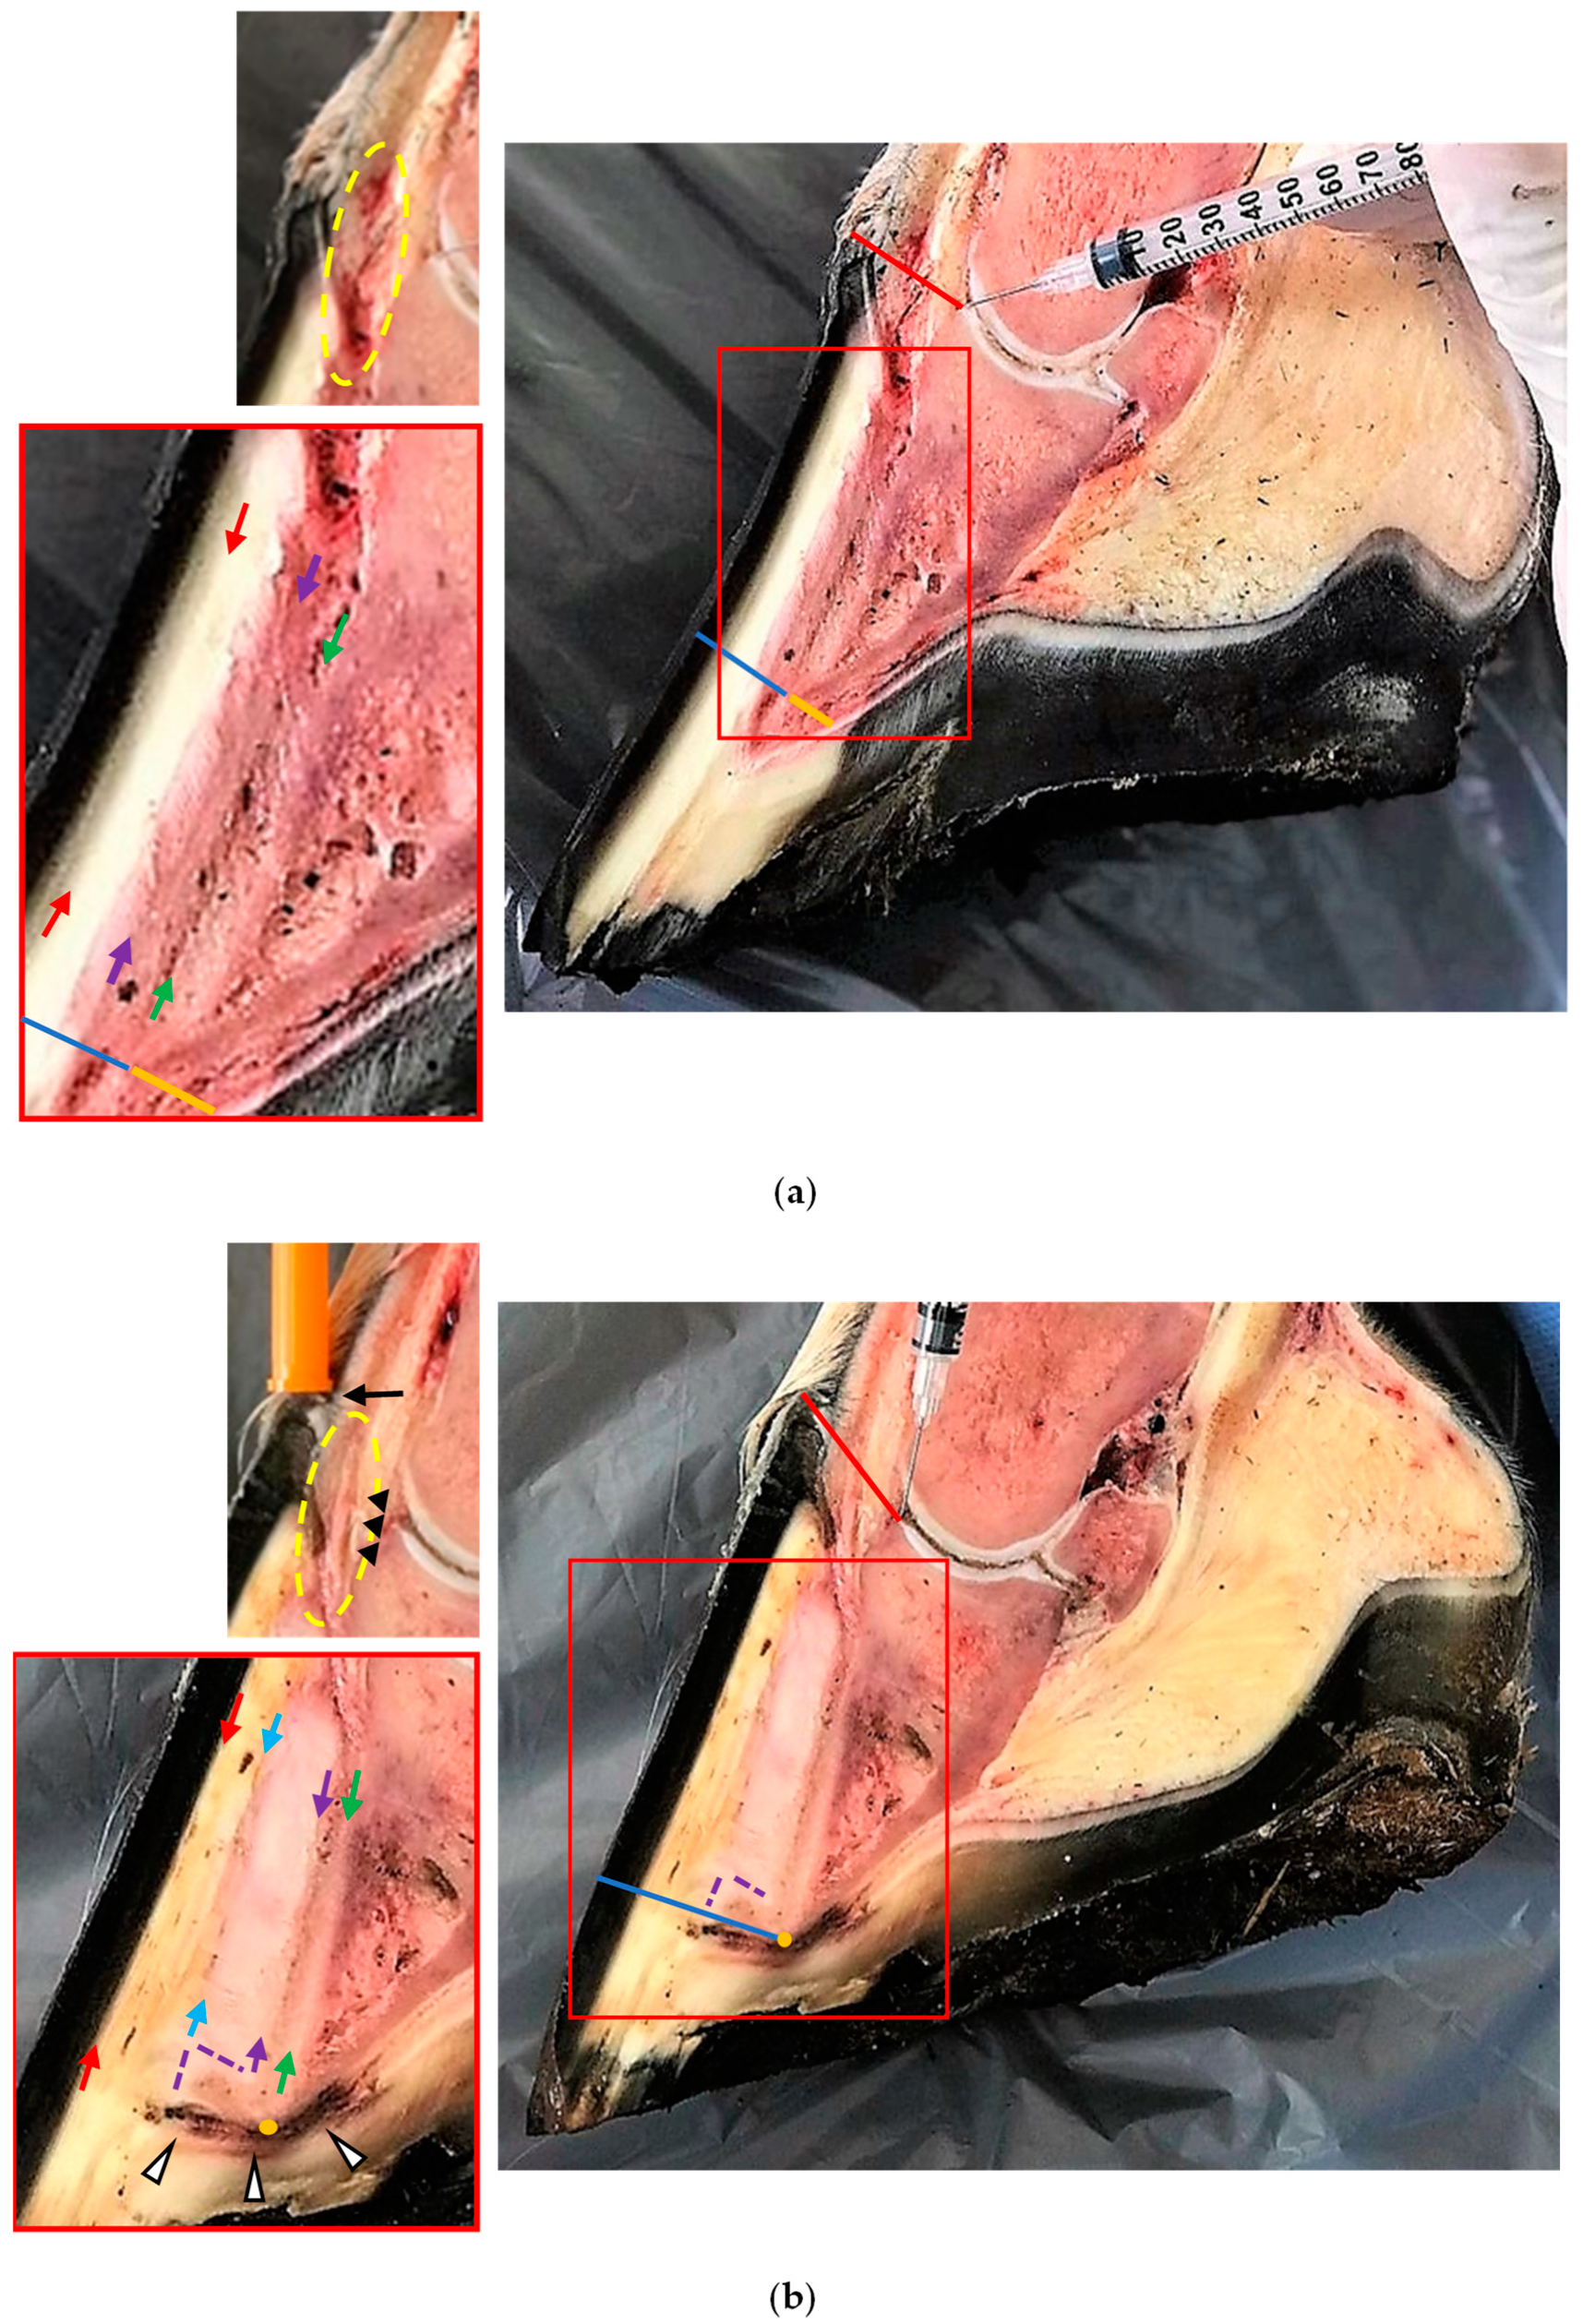

2. Materials and Methods

2.1. Anatomical Pieces and Alive Horse Hooves

2.2. Measurements of the Hoof Internal Structures and Ultrasonographic Ratios